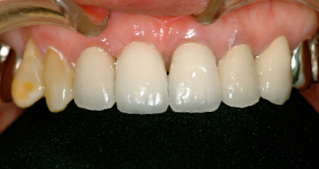

前歯の差し歯が折れて

抜歯した症例です

どの歯がインプラントかわかりません。

特に前歯のインプラントは審美性が

求められるので、

繊細な技術が必要です。